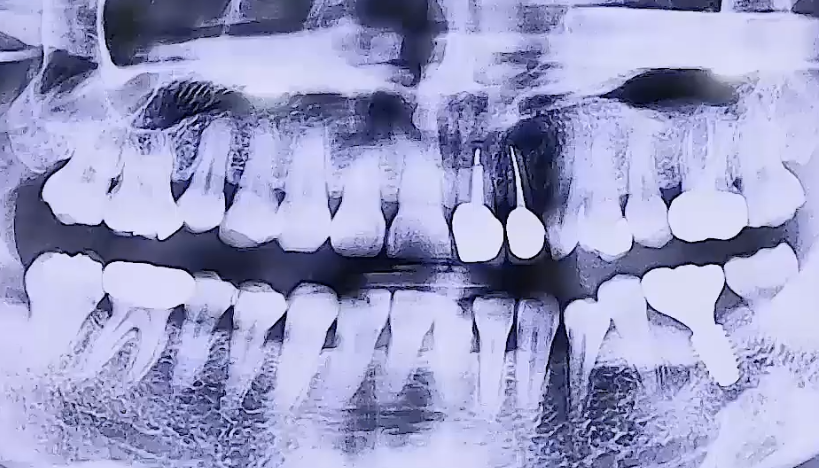

BEFORE

왼쪽 아래 어금니 통증으로 내원해주신 환자분이십니다.

왼쪽 아래 뒤에서 두번째 큰 어금니를 타 치과에서 신경치료 후

보철치료까지 마무리하신 상태였는데, 그 주변 잇몸에 염증이 생기며

굉장히 부어 오르고 통증이 심했던 것으로 확인되었습니다.

해당 치아는 겉으로는 보이지 않는 잇몸 속에 염증이 생긴 것이기 때문에

잇몸치료를 해도 치아가 안 좋아질 가능성이 크므로 발치 후 임플란트를 결정하였습니다.

또한 위 앞니는 깨져있어서 기둥을 세우고 치아를 복원하는 보철치료를 진행하였어요.

오른쪽 아래 매복사랑니가 앞쪽 치아를 향해 옆으로 누워 아주 조금 나와 있어,

그쪽에 음식물이 끼면서 염증이 생길 수 있기 때문에 발치를 해드렸습니다.